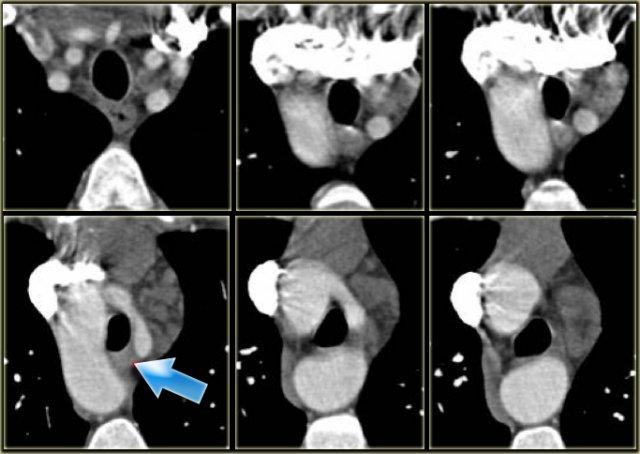

Double Arch with Atretic Segment

Occasionally the double arch can have an atretic segment.

You should not confuse it for a right arch.

The left arch is just very small and there is still a four vessel sign.

On the left a dominant right arch and a small left arch.

The atretic segment is marked by the arrow.

Notice the four vessel sign.

On a posterior view the interruption is nicely demonstrated.

Remember that there is still a ring, so there is still obstruction.

Another case on the left.

Do not call this a right arch.

It still is a double arch and there is a atretic fibrotic segment on the posterior side of the left arch, that completes the ring.

Same patient.

Always look at the airways.

On the recoonstruction the impression on the trachea is better appreciated.